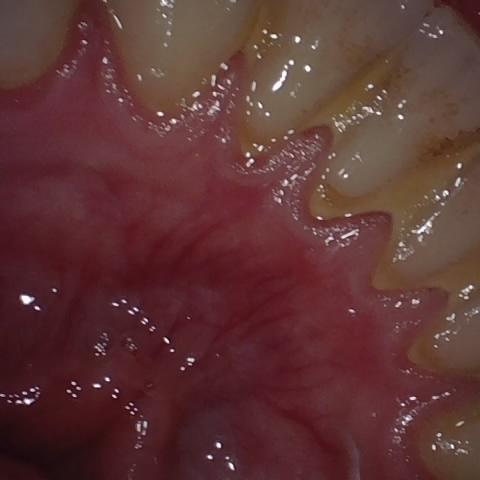

Annotated as "Good"